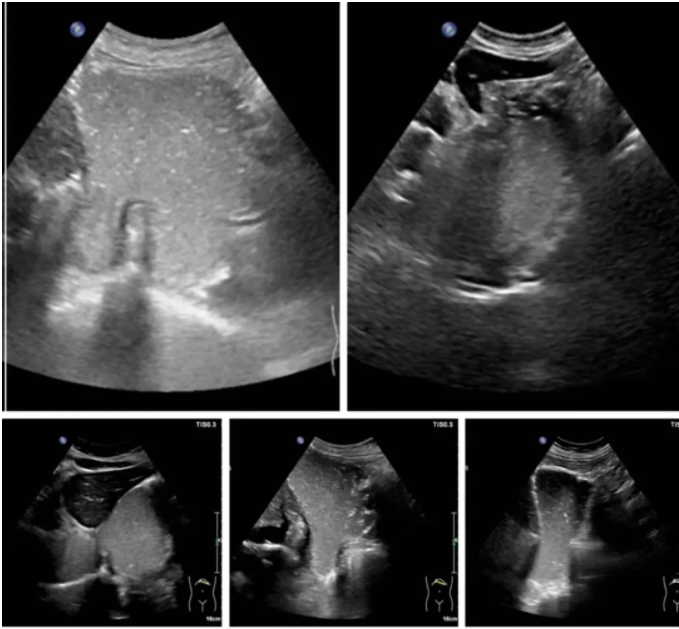

下图是不同表现的滑动型食管裂孔疝:宽窄不一的食管裂孔管径、大小不一的疝囊、或正常或变钝的HIS角,部分病例可见疝囊壁与胃壁回声及厚度一致的延续: